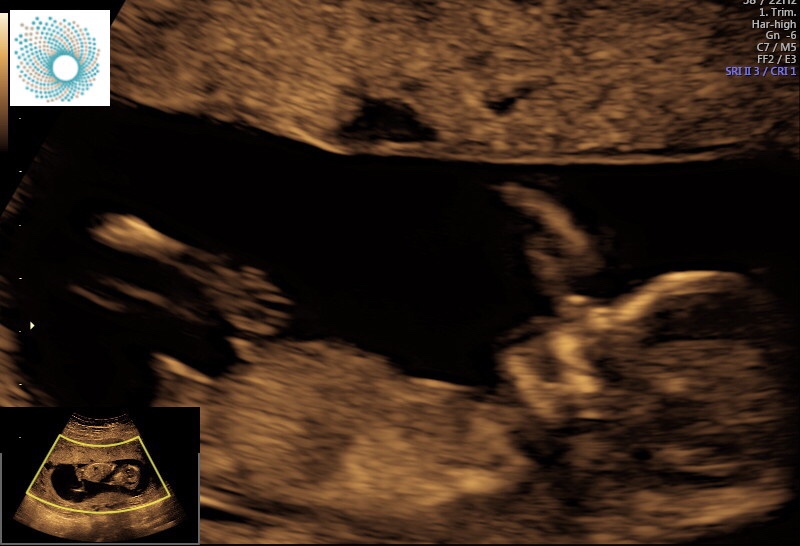

Taken at 12+4. Please let me know your guesses :)

tentative pink lean, but much earlier than I like to guess

Maybe girl but still time for the nub to rise.